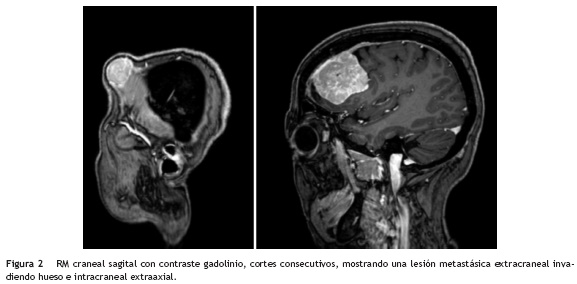

Cinco años y medio tras el debut y en curso de imatinib, se objetivó crecimiento de la lesión hepática y aparición de dos pequeños implantes abdominales. Ante la progresión hepática y peritoneal, se decidió escalada de dosis de imatinib a 400 mg/12 h. Poco tiempo después, manteniéndose estable la enfermedad a nivel abdominal, la paciente refirió crecimiento de una tumoración en región frontal derecha. En la exploración se puso de manifiesto un nódulo de consistencia elástica, de 3 cm de diámetro máximo, en dicha localización. Se realizó PAAF, que fue compatible con metástasis de GIST. La RMN craneal evidenció una lesión isointensa en T1, que captó contraste de forma homogénea, de localización frontal derecha, intraósea, que se extendía tanto intracraneal como extracranealmente (fig. 2).

En los EGIST la clínica más frecuente es dolor y/o masa abdominal3, debido al gran tamaño que alcanzan las lesiones. En muchos casos, como ocurrió con esta paciente, el diagnóstico definitivo se difiere a la cirugía, generalmente tras unos meses de tratamiento sistémico neoadyuvante. El lugar más frecuente de diseminación es el hígado, aunque también se describen metástasis ganglionares, poco habituales en los GIST4. Aunque muy raras, las metástasis óseas de GIST sí se han descrito, incluso en huesos planos como la calota craneal10,11, siendo este el primer caso documentado en EGIST con diseminación ósea exclusiva a dicho nivel. El diagnóstico diferencial de estas lesiones craneales se facilita mediante el estudio con RMN cerebral que permite delimitar las lesiones y localizar la base de implantación en leptomeninge de otro tipo de tumores, como son los meningiomas11. En este caso, la imagen ofrecía duda diagnóstica entre un meningioma angioblástico y una metástasis ósea con componente extracraneal, subgaleal e intracraneal. Al contrario que en los casos publicados, en esta paciente se realizó exéresis de la lesión ósea, lo que ha permitido un prolongado intervalo libre de síntomas neurológicos.